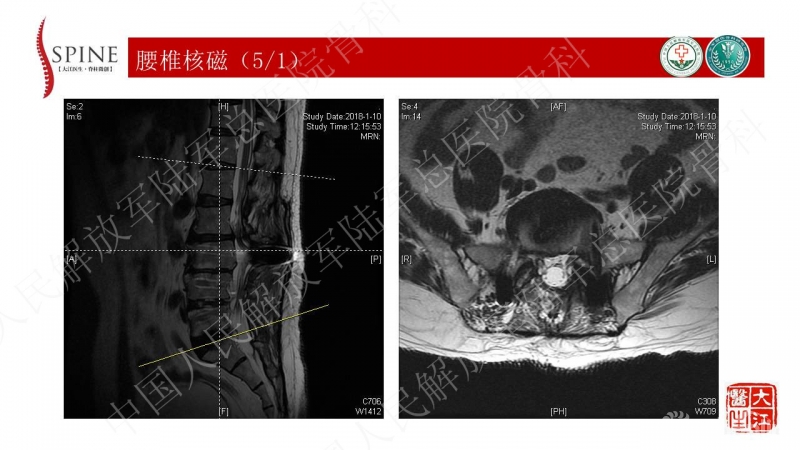

考虑患者合并腰2-3邻近节段征象及腰5-骶1节段断棒的表现,首先需要明确既往是否有间隙性跛行的症状。因患者查体有下肢神经功能损害体征,又不是单一根损害的体征,是颈椎伤后的残留,还是上腰椎椎管狭窄的神经损害,需要鉴别。根据患者病理征阳性的表现,若既往无跛行的症状,则可将目前下肢神经功能损害归因于颈椎伤后的表现。

患者主诉为腰痛伴下肢疼痛,腰痛为主,翻身活动、下地时疼痛加重。体格检查也为下腰段的叩压痛,影像可见腰5-骶1断棒。断棒的原因都是力学应力相关的原因,而患者SVA(矢状位垂直轴)不大,全身平衡状态尚可。结合CT表现,应怀疑腰5-骶1节段未融合。

本病例的焦点在患者腰痛的原因,患者明确其腰痛非慢性腰痛,伤后出现。结合病史、体格检查、断棒的表现,主要考虑下腰段的原因。要考虑两个原因,一是腰5-骶1的未融合,断棒后不稳,局部应力集中。二是断棒后局部异常活动,带动瘢痕牵拉硬膜囊及神经根的向背侧牵拉,这种异常活动在残留小关节的抵挡下会引起严重卡压,而出现下肢的疼痛、甚至神经功能损害等。患者行原术区内固定取出,腰5-骶1内固定术,术后取得良好效果,证实患者本次疼痛病因为腰5-骶1节段断棒后应力集中、异常活动。